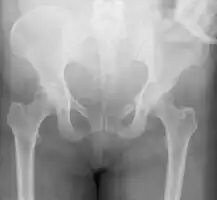

A pelvic X-ray showing an open book fracture

Open book fracture

One specific kind of pelvic fracture is known as an 'open book' fracture. This is often the result from a heavy impact to the groin (pubis), a common motorcycling accident injury. In this kind of injury, the left and right halves of the pelvis are separated at front and rear, the front opening more than the rear, i.e. like an open book that falls to the ground and splits in the middle. Depending on the severity, this may require surgical reconstruction before rehabilitation.[10] Forces from an anterior or posterior direction, like head-on car accidents, usually cause external rotation of the hemipelvis, an “open-book” injury. Open fractures have increased risk of infection and hemorrhaging from vessel injury, leading to higher mortality.[11]